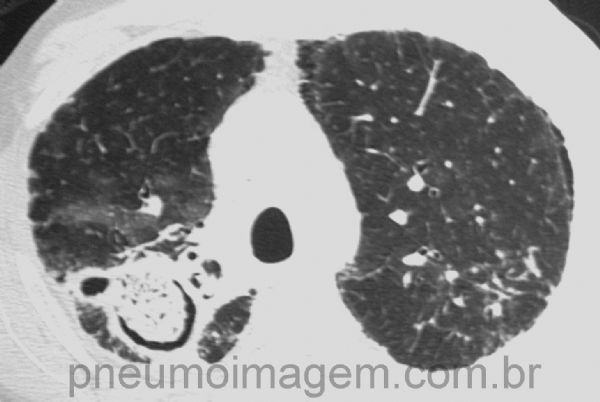

Corte tomográfico mostrando a mesma lesão da radiografia acima. Cavidade pulmonar preexistente nos casos de aspergiloma na maioria das vezes é devida à tuberculose, mas também pode ocorrer na sarcoidose, enfisema, bronquiectasia ou qualquer outro processo necrosante pulmonar.

CT slice showing the same injury of radiography above. The preexisting pulmonary cavity is most often due to tuberculosis, but can also occur in sarcoidosis, emphysema, bronchiectasis or other lung necrotizing process.

Bola fúngica crescendo no interior de cavidade residual tuberculosa formando o sinal da meia lua ou sinal em crescente (sinal de Monod). Cavidades por sarcoidose, enfisema pulmonar ou decorrentes de outros processos necrosantes pulmonares podem também ser sedes de aspergiloma.

Fungal ball growing inside of residual tuberculous cavity and causing the Half Moon sign or crescent sign in (Monod sign). Cavities by sarcoidosis, pulmonary emphysema or under other necrotizing pulmonary disease can also be established aspergilloma.